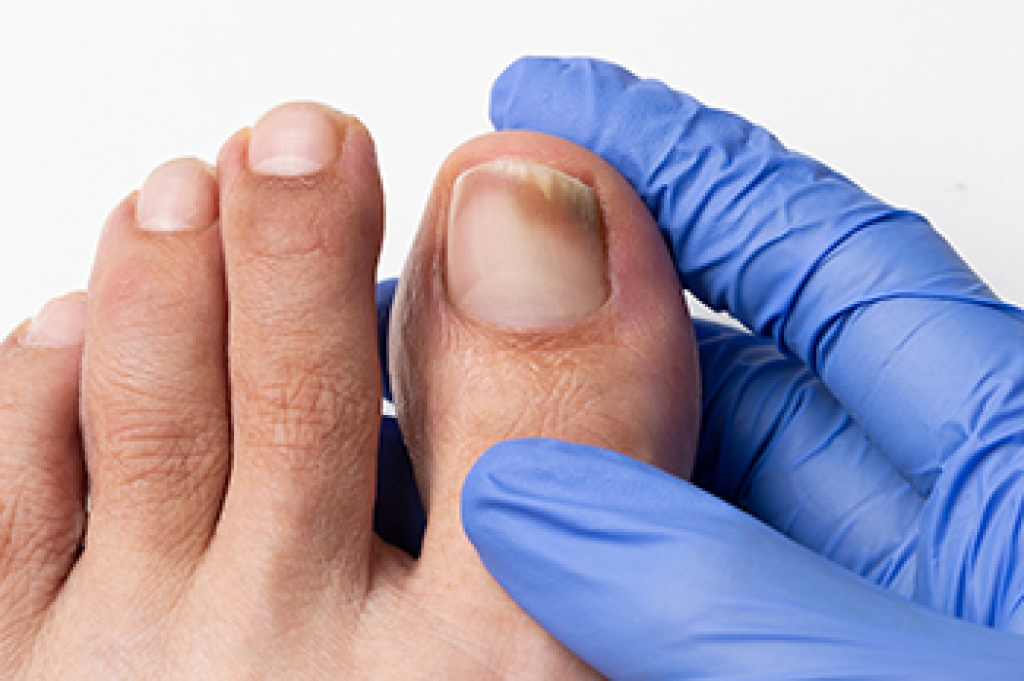

Sesamoiditis is an irritation of the two sesamoid bones that are located beneath the first metatarsal head of the foot. It leads to pain that can be particularly bothersome during activities like walking or running. These tiny bones, each about the size of a kernel of corn, play a significant role in foot movement. They can become painful due to trauma, foot structure changes, or repetitive stress. Sesamoiditis is often seen in dancers, runners, and those who frequently wear high heels. Symptoms can include localized pain beneath the big toe, swelling, and tenderness that worsens with pressure. Diagnosis typically involves a clinical evaluation by a podiatrist, sometimes supported by imaging tests to rule out fractures or other conditions. Treatment focuses on reducing pressure on the sesamoids through footwear modifications, including supportive shoes and custom orthotics. If you have pain under the big toe, it may be related to the sesamoid bones, and it is suggested that you schedule an appointment with a podiatrist for an exam and treatment.

Treatment for sesamoiditis is non-invasive and simple. Doctors may recommend a strict rest period where the patient forgoes most physical activity. This will help give the patient time to heal their feet through limited activity. For serious cases, it is best to speak with your doctor to determine a treatment option that will help your specific needs.